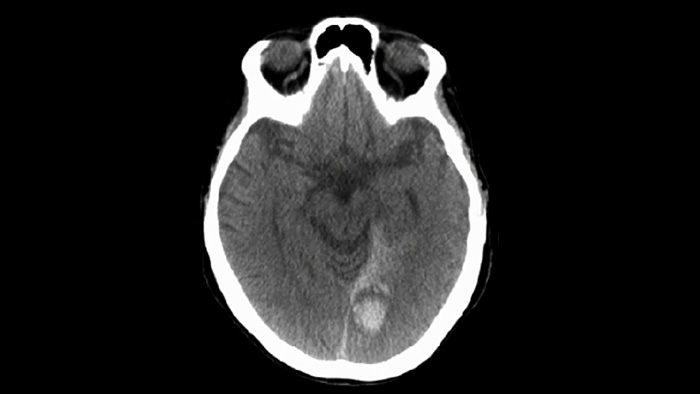

Используйте SmartCT для визуализации мягких тканей при исследовании сосудов, чтобы убедиться в успешности лечения и осуществить проверку на наличие кровотечений.